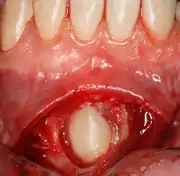

التهاب حوائط التاج (التواج)

التواج هو التهاب في الأنسجة التي تغطي التاج من الضرس المنطمر. و بالعادة تتكوّن بفعل الميكروبات الفموية العادية. لمعظم الناس يكون هنالك توازن بين دفاعات المضيف والميكروبات الفموية، ولكن إذا تم اختراق دفاعات المضيف في حالات الأمراض الطفيفة- كالإنفلونزا أو عدوى الجهاز التنفسي العلوي- تنتج التهاب بحوائط التاج. و كسبب آخر شائع هو انحشار الطعام تحت الشرائح اللثوية (تسمى أيضا بالأطبقة أو الأغلفة). التهاب حوائط التاج ممكن ان تكون خفيفة أو شديدة. و في أبسط أشكالها هي مجرد تورم في الأنسجة الموضعية مع ألم، بينما في الحالات الشديدة التورم يكون أكبر وفي بعض الأحيان يسبب ما يعرف بالضزز (تشنج يمنع فتح الفم).